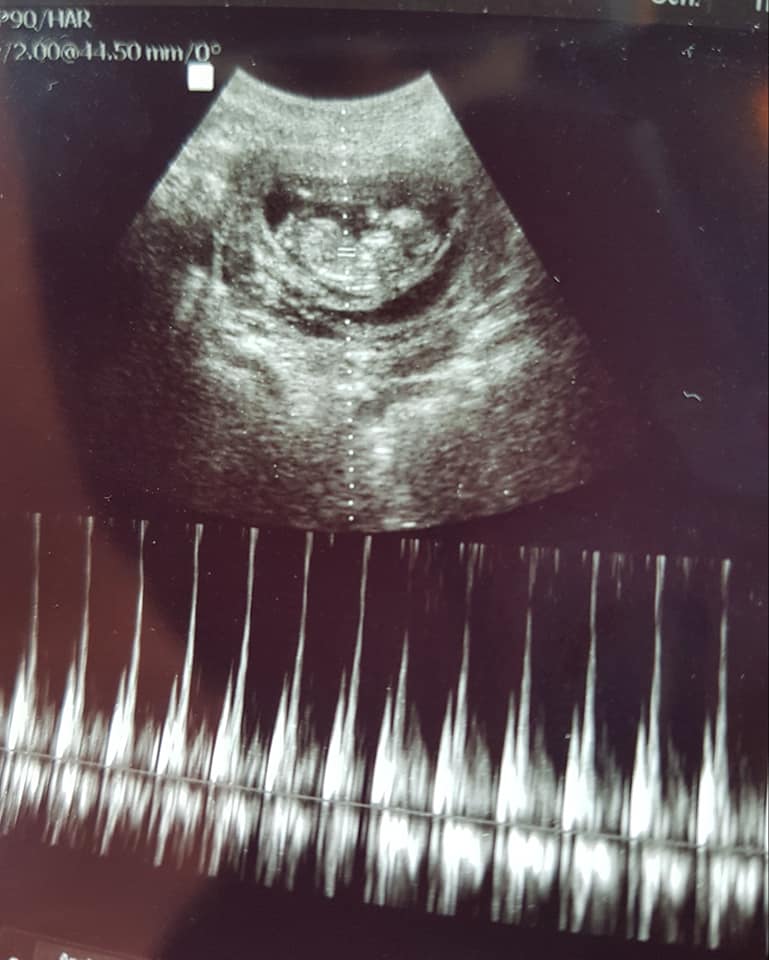

Scan done at 12weeks1day. I think it looks pretty obvious but want confirmation. We have 3 girls alreadyAttachment 40192Attachment 40191

I would give a VERY tentative blue lean but please don't get your hopes up or paint the nursery yet because the baby is curled up, it's early, and the photos are grainy.

Just back to say i got my NIPT result back and it's a healthy BOY:ttcboy::xy: